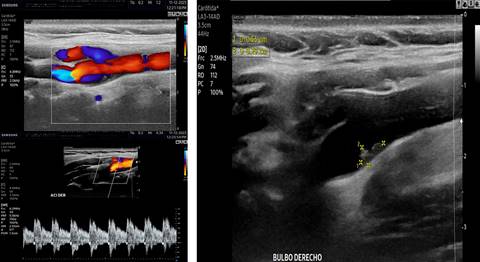

Femenino de 40 años con ataque isquémico transitorio (AIT), en la que se efectuó ultrasonido y angiotomografía que mostraron banda carotídea ipsilateral. La displasia fibromuscular atípica del bulbo o banda carotídea es una patología no ateromatosa implicada en la aparición de infartos cerebrales. La banda carotídea se define como un defecto de llenado lineal en forma de estante en la cara posterior del bulbo de la arteria carótida interna mediante angiotomografía (Figura 1) y/o ultrasonido (Figuras 2 y 3), se reconoce cada vez más como una causa de accidente cerebrovascular criptogénico y/o AIT recurrente, pero la evidencia sigue siendo escasa. Se observa en ambos géneros, con distribución 2:1 a favor del femenino y mayor incidencia en personas de color; cuando son bilaterales (60%) presenta mayor longitud en el lado ipsilateral sintomático que en el contralateral (3-4.5 mm vs 1.85-2.9 mm), observando trombos superpuestos hasta en 30% de los casos con banda carotídea sintomática. A pesar de la recurrencia y gravedad de los accidentes cerebrovasculares originados por embolización asociada con banda carotídea, no existen recomendaciones sobre la mejor estrategia para su manejo; el tratamiento con agentes antiplaquetarios previene la aparición de accidentes cerebrovasculares, pero el tratamiento radical sigue siendo quirúrgico y/o endovascular.

Figura 2: A) Imagen Doppler color y espectro que demostraron cambios en la dirección del flujo vascular adyacente a la protrusión intimal y de flujo turbulento en ambas direcciones. B) Imagen por ultrasonido 2D longitudinal que demostró en la pared posterior del bulbo carotídeo derecho una banda isoecogénica intimal que protruye hacia el lumen arterial.